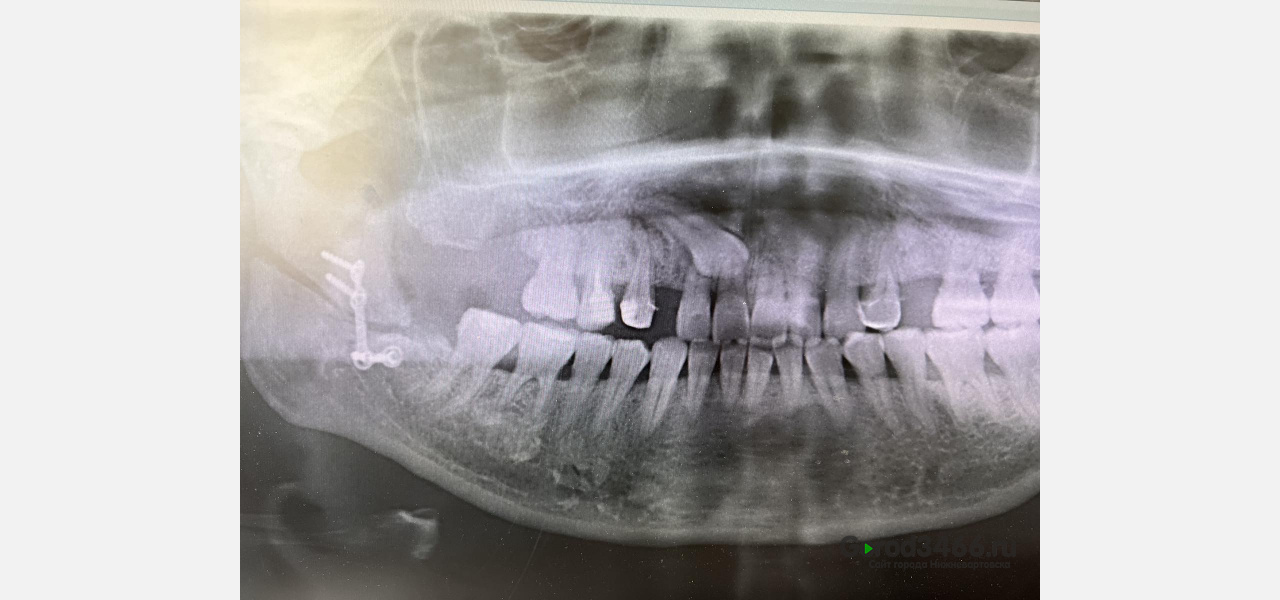

У 47-летней пациентки была доброкачественная опухоль 20-летней давности. Все эти годы женщина не обращалась к медикам, так как новообразование не доставляло сильного дискомфорта. Однак, в этом году, когда пациентка пришла на консультацию к челюстно-лицевым хирургам, опухоль уже мешала ей открывать рот и причиняла неудобство.

Поскольку опухоль проникла глубоко, операция выполнялась с рассечением нижней челюсти на всём протяжении.

«Особенность данной операции в том, что она выполнена только из полости рта, без разрезов на лице. Эта методика не только более косметична, но и позволяет избежать такого осложнения, как повреждение лицевого нерва и ускоряет послеоперационную реабилитацию больных», - рассказали в Департаменте здравоохранения ХМАО.